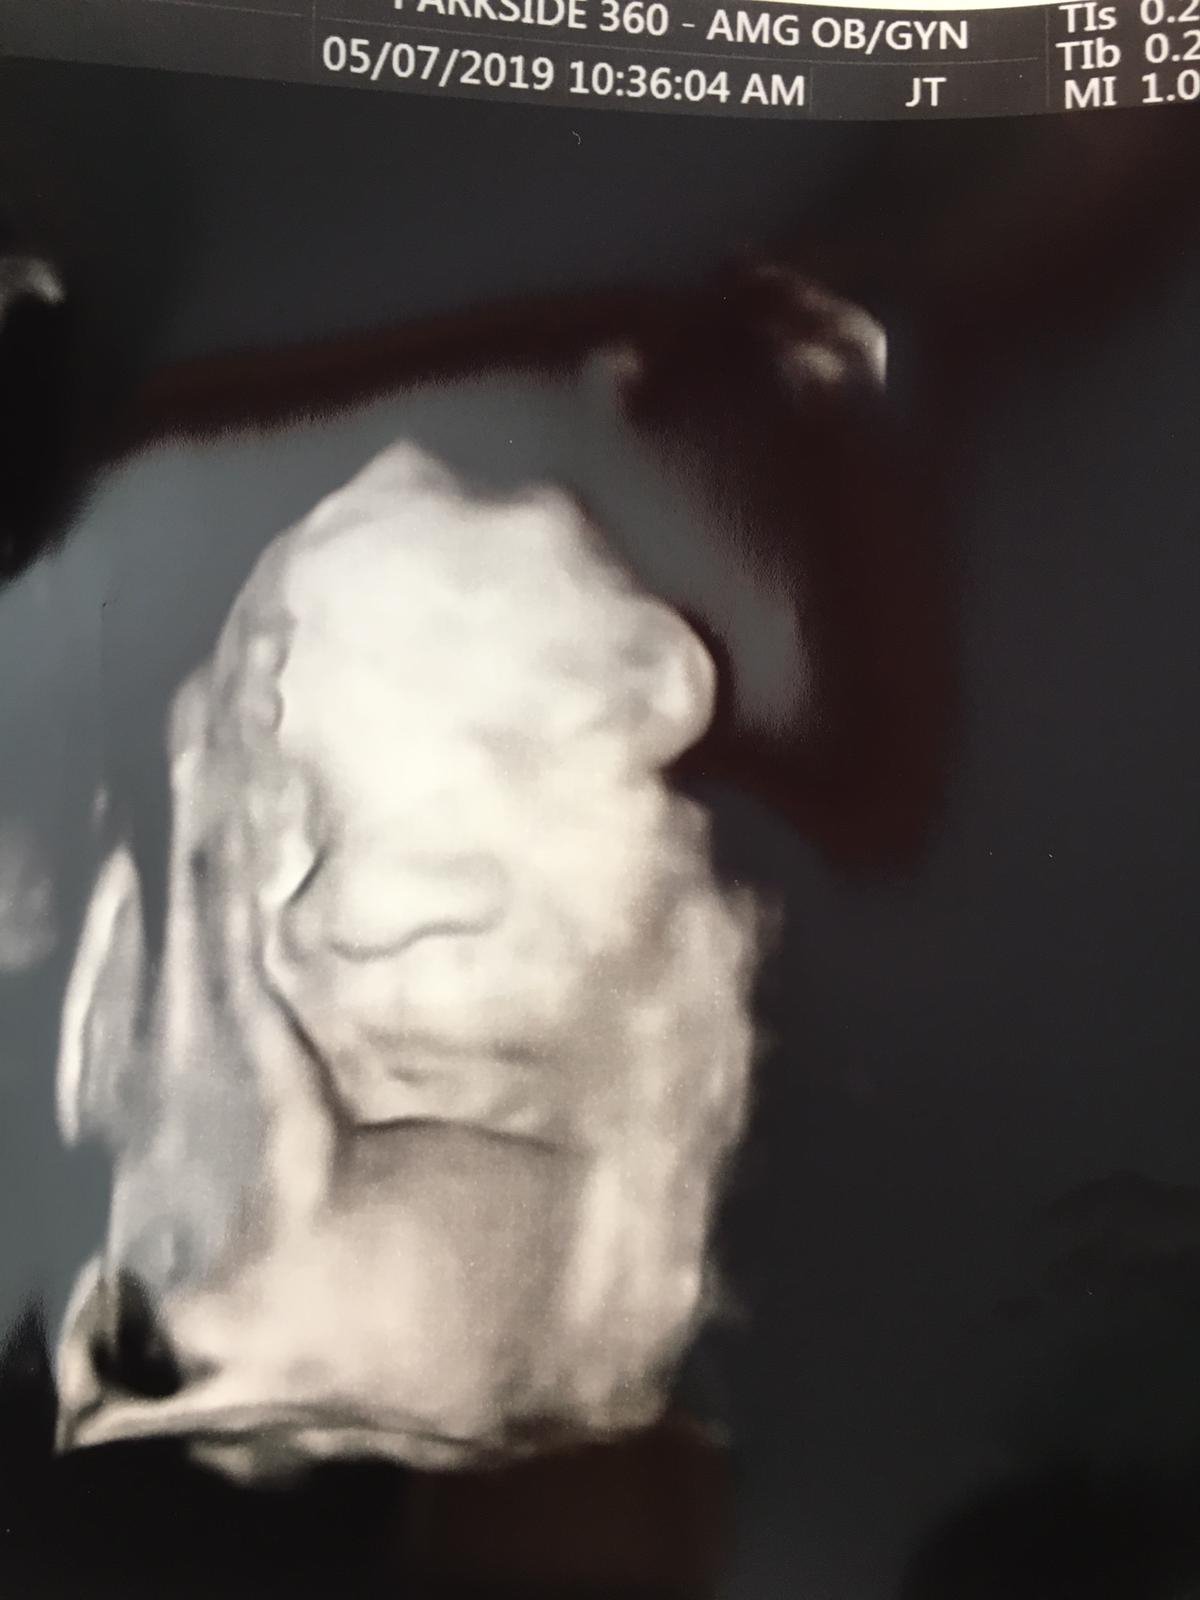

I had my weekly appointment today. All looks ok and I might go full term until 40 weeks. We got picture of him, he still has hands on his face but clearest picture I have got till date. He removed hand when ultrasound technician knocked on his hand but swiftly put it back, she couldn’t take a picture of face without the hand.

Got my GBS test done and dilation check today. My cervix is still closed. Pic in the spoiler